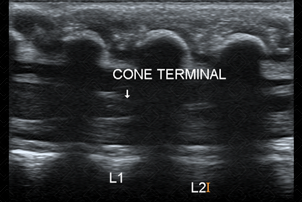

Texto alternativo para a imagem Figura 3. Créditos: Dra. Elazir Mota - Rio de Janeiro/RJ

Descrição das figuras 2 e 3: Ultrassonografia da coluna lombar evidenciando cone medular, tópico (ao nível de L1-L2) (seta branca). [cms-watermark]